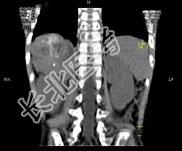

- 多项选择题男,5 岁, 消瘦、贫血、纳差和腹部包块3个月,CT检查如图, 下列说法正确的是  (    )

- A、右侧腹腔内可见一巨大软组织肿块影,其边界欠清楚

- B、肿块密度不均匀,可见片状的较高密度,考虑为出血,也可见点状的钙化影

- C、该病灶来源于肝脏,考虑为肝母细胞瘤

- D、该病灶来源于右肾上腺,考虑为神经母细胞瘤

- E、该病灶来源于右肾,考虑为肾胚胎瘤